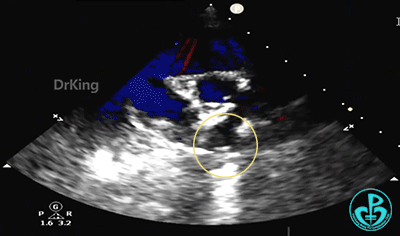

锁定后,主动脉短轴切面显示封堵器呈Y字型抱住主动脉根部。

牵拉稳定,锁定成功。

牵拉试验,封堵器位置固定,未见明显位移及形变。

主动脉短轴切面显示封堵器呈Y字型抱住主动脉根部,夹持稳定。

2. 该患儿缺损部位紧邻主动脉根部,使用金属封堵器进行封堵可能增加封堵器与主动脉根部之间的接触风险,对主动脉造成压迫,引发组织磨蚀、血栓等长期并发症。基于孩子远期健康的考量,本例患儿选择了可降解封堵器进行封堵。可降解房间隔缺损封堵器专利成型锁定设计,可确保封堵器稳定夹持主动脉根部;同时其贴壁、贴合效果好,锁定后封堵器紧密贴合于缺损部位利于内皮化,使其在封堵靠近主动脉根部等复杂房缺治疗中临床优势显著。